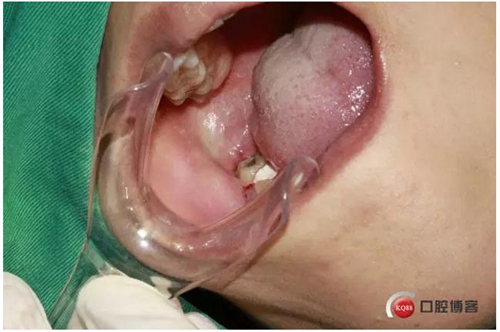

4%鹽酸阿替卡因腎上腺素局部麻醉,

口內(nèi)照片,48遠(yuǎn)中三分之一覆蓋部分牙齦。